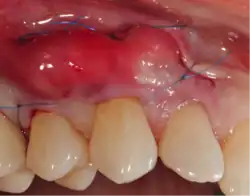

Traditional gum grafting will have a piece of the gums harvested from the roof of the mouth and sutured facing the exposed root to increase the lost keratinized tissue.[11] The limitation in quantity and the morbidity are the limiting factor of this technique. Allografting techniques (skin from cadavers bought from tissue banks) are used as well to supply the surgeon with larger amount of tissues when needed in larger cases,[12] but the type of healing and the risk of possible disease transmission should be considered and disclosed to the patient when opting for such technique.[13]

A small amount of blood (10 millilitres (0.35 imp fl oz; 0.34 US fl oz) per tube) is harvested and spun in a centrifuge for eight minutes at 1300 RPM. A fibrin clot packed with blood-derived growth factors, extra cellular matrix and hematopoietic stem cells is fabricated and implanted into the gums above the area of gum recession. Advanced platelet-rich fibrin will promote the patient's own gums to fabricate more gum thus eliminating the need to harvest gums from the roof of the mouth or the use of allografting tissue.